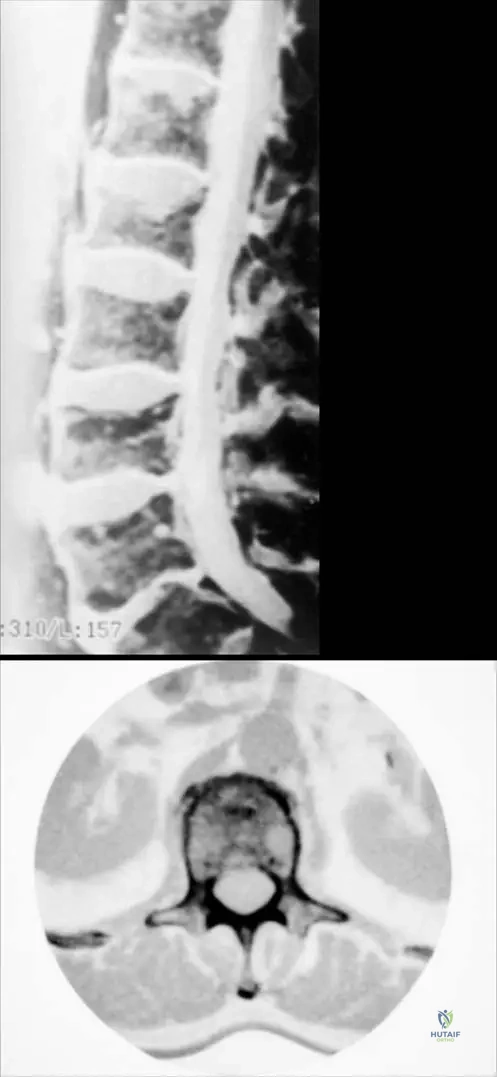

Question 43

A 45-year-old immigrant man presents with chronic low back pain, night sweats, and weight loss over several months. Physical examination reveals tenderness over the thoracolumbar spine and a gibbus deformity. Radiographs show destruction of multiple vertebral bodies with associated disc space narrowing and a large paraspinal soft tissue mass.

View Answer & Explanation

Correct Answer: C

A 6-year-old male presents with a 3-day history of fever, malaise, and severe pain in his right distal femur. On examination, the area is warm, swollen, and exquisitely tender to palpation. He refuses to bear weight on the affected leg. Laboratory tests reveal an elevated white blood cell count, ESR, and CRP. Radiographs show subtle soft tissue swelling around the distal femur, with no obvious bony changes. An MRI of the femur demonstrates diffuse bone marrow edema and a subperiosteal fluid collection in the distal metaphysis.

Rationale: The clinical presentation of fever, localized bone pain, refusal to bear weight, elevated inflammatory markers, and radiographic findings of soft tissue swelling with MRI showing bone marrow edema and subperiosteal fluid collection in the metaphysis of a long bone in a child are classic for acute hematogenous pyogenic osteomyelitis. This condition is typically caused by bacterial infection spreading through the bloodstream to the bone. Septic arthritis (A) would primarily involve the joint space, though it can occur concurrently. Cellulitis (B) is a soft tissue infection without bone involvement. Ewing's sarcoma (D) is a bone tumor that can mimic infection but typically presents with more chronic symptoms and characteristic "onion-skin" periosteal reaction on X-ray. A stress fracture (E) would not present with fever or elevated inflammatory markers.